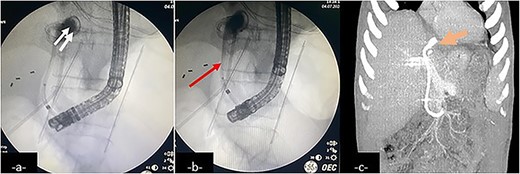

Upon further examination, the patient’s blood tests showed elevated inflammatory markers, and imaging studies revealed atelectasis in the right lower lung lobe, pleural effusion, and a subphrenic collection (Fig. 2). A computed tomography (CT) scan confirmed the presence of an intrahepatic collection communicating with the pleural cavity, indicating a potential BBF (Fig. 3) which was confirmed on magnetic resonance imaging (MRI) (Fig. 4). A drain was inserted under CT guidance (Fig. 5), and an endoscopic retrograde cholangiopancreatography (ERCP) revealed spontaneous bile leakage from the duodenal bulb. A stent was placed to drain the biloma (Fig. 6). Surgical intervention was avoided due to the patient’s liver condition.

An endoscopic retrograde cholangiopancreatography (ERCP) showing contrast leakage from left-sided bile duct (a, double arrow) with duodenal fistula communicating with the biloma, drained by an inserted stent (b, arrow). Follow-up coronal CT-scan reconstruction after ERCP shows the internal drainage (c, large arrow).